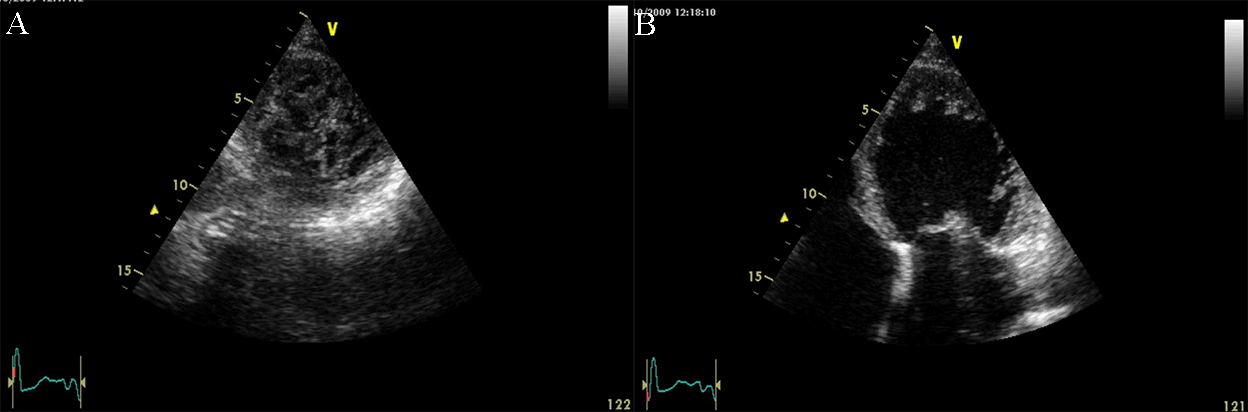

Fig. 2.Echocardiographic aspect of DCM in a patient with idiopathic dilated cardiomyopathy. (A) Parasternal short axis at the level of the mitral valve, diastolic frame showing a dilated left ventricle. (B) Parasternal short axis at the level of the mitral valve, systolic frame showing the small difference between the end-diastolic and end-systolic diameter of the left ventricle due to reduced contractility.